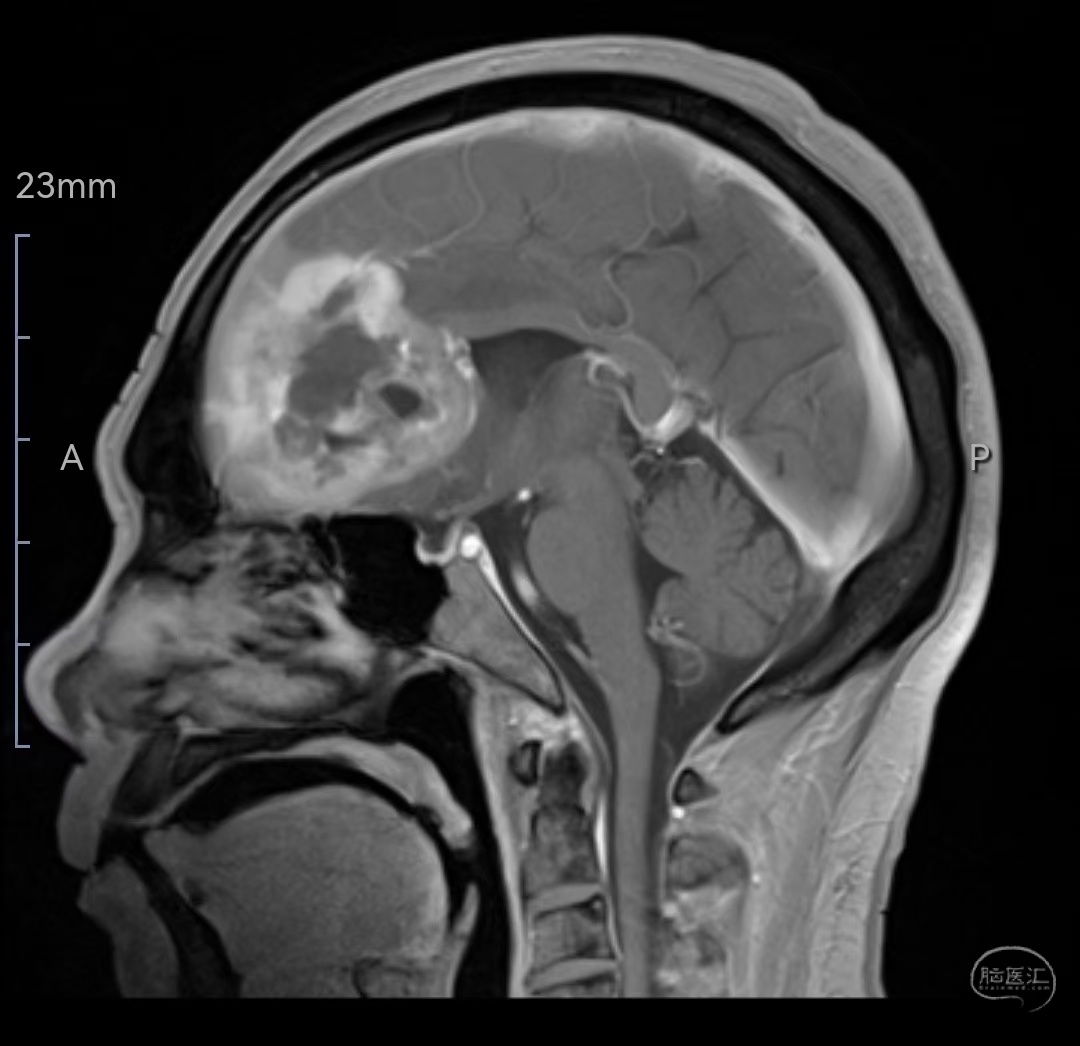

MRI增强矢状位示肿瘤明显强化,侵犯压迫至胼胝体嘴、膝部